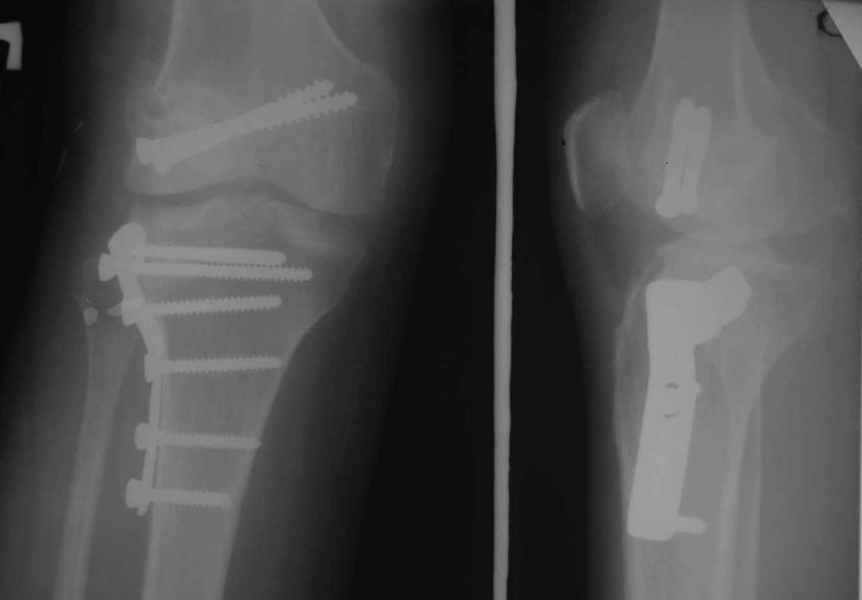

Как вариант решения прогрессирующей вальгусной деформации коленного сустава я бы предложил косую остеотомию дистального отдела бедра с фиксацией пластиной и компрессирующим винтом.

Взгляните на снимки , может быть это вам поможет.

Около 5 лет применяю этот тип дистальной остеотомии бедра для коррекции механической оси Н/К ( более 20 случаев) - достаточно эффективная операция.

Уважаемый Евгений ! Спасибо за ответ, но мне представляется, что в нашем случае основной проблемой является не столько прогрессирующий вальгус конечности, сколько несросшийся перелом мыщелка бедра и дефект мыщелка большеберцой кости - вероятно первичная репозиция выполнялась без пластики.

На своем горьком опыте убедился, что синтезировать мыщелковые импрессионные внутрисуставные переломы б\б кости без костной пластики - дело неблагодарное, рецидивируе деформация, мыщелок всегда *проваливается*. Чистые split type переломы можно ограничиваться и одной только межфрагментарной компрессией.

Может стоит сначала добиться сращения наружного мыщелка бедра( костная пластика) и коррекции оси?

Мне представляется, что прогрессирующий вальгус и обусловлен несросшимся переломом мыщелка бедра (томограммы -зона межфрагментарного склерозирования), а циклические нагрузки на сустав во время ходьбы усугубляют ситуацию. Как вы думаете, в этой ситуации насколько вероятен риск развития аваскулярного некроза мыщелка бедра?

Относительно "рубцовой подушки" я имел в виду остатки мениска ( частично вколоченного в дефект мыщелка и фрагменты хряща), все таки на рентгенограммах суставная щель в этом отделе чем то заполнена. Что касается некроза мыщелка бедра, то мне кажется он уже наступил - томограмма ноябрь5.

С учетом всего сказанного - наличия прогессирующего вальгуса конечности, довольно приличного объема движений, имеющегося, вероятно, некроза мыщелка бедра, наиболее рациональным представляется удалить пластину с б\б кости, произвести остеотомию б\б кости с коррекцией вальгуса, разгрузив тем самым наружный отдел сустава, и синтезировать фрагменты голени накостным фиксатором. Максимально тано начать восстановление движений в суставе. Скорее всего рано или поздно речь о протезировании всеже возникнет, но мы хотя бы будем иметь приличную ось конечности.

Тут ситуация совсем другая. Деформация не около-, а самая что ни на есть внутрисуставная. Покорректировать внешний вид конечности путем остеотомии дистального отдела бедра и high tibia (плюс или минус клин, одномоментно-постепенно, аппарат-пластина-стержень - дело третье) не сильно сложно, но это не решение проблемы. У больной, по

сути отсуствует латеральный отдел коленного сустава, что требует костно-пластических вмешательств непосредственно на артикулирующих

поверхностях.